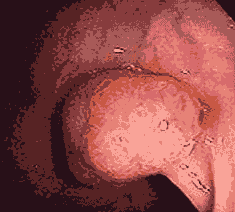

肠息肉是比较容易发生的肠道疾病,有单发,也有多发,息肉的大小不一,会出现大便出血、排便时肛门疼痛、粘液便等情况。

洛阳东大肛肠医院医生介绍:多发性肠息肉,即为多个息肉,非单个。

洛阳东大肛肠医院针对传统检查易误诊、漏诊的弊端,引进了韩国电子肛门镜,采用1200万像素的医用摄像技术,深入直肠,能清晰看到病灶部位、病变情况和息肉的数量,确诊率高,用时3-5分钟,预约无需排队,20分钟拿检查结果,无痛舒适。